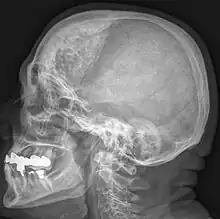

Hyperostosis frontalis interna is a common, benign thickening of the inner side of the frontal bone of the skull. It is found predominantly in women after menopause and is usually asymptomatic. Mostly frequently it is found as an incidental finding discovered during an X-ray or CT scan of the skull.

Additional images